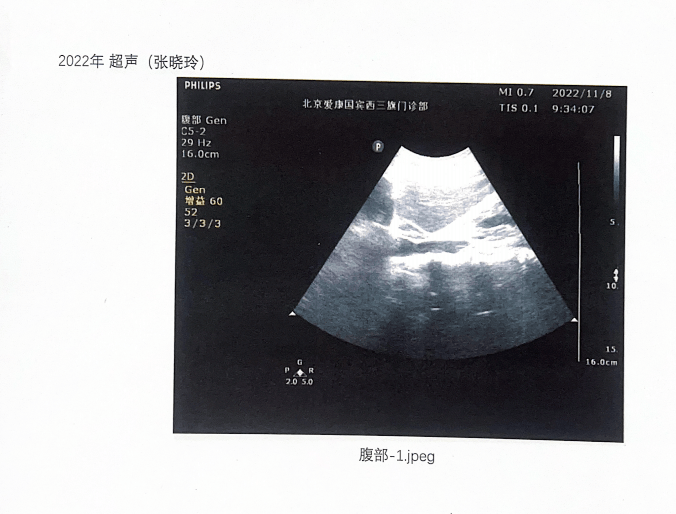

不过12月13日,张晓玲告诉记者,在北京市卫健委的主持下,爱康国宾在12月8日提供了2021年、2022年、2023年的三年超声影像图片复印件,且图片上没有姓名、ID和出生日期。张晓玲称,自己对这份模糊图片不能认可,已经向卫健委反映,收到的答复是会责令处理。记者在三份超声影像图片上看到,里面有标注时间和爱康国宾门诊部名字,但没有显示体检人身份信息。

▲张晓玲律师2022年的超声图片 受访人供图